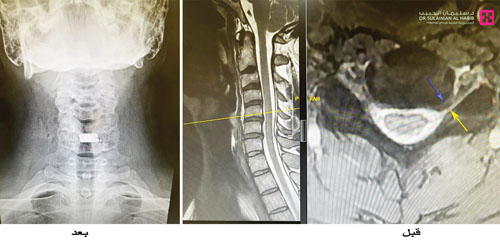

وأوضح د. علاء أنه تم إجراء الفحوصات والأشعة اللازمة للمريض وتبين وجود بروز للغضاريف على أكثر من مستوى، وتضيق حاد وانزلاق غضروفي في قناة العصب السادس الأيسر، وهو ما يفسر الألم والتنميل في اليد اليسرى وكذلك جزء من آلام الرقبة المزمنة التي يعاني منها المريض. وأستطرد د. علاء قائلاً أن الفريق الطبي المعالج ناقش الخيارات العلاجية المتاحة لاستبدال الغضروف بدعامة ثابته أو ديسك صناعي مرن واستقر رأي الفريق على اختيار الديسك الصناعي للمحافظة على مرونة الحركة بالرقبة كون المريض لا زال شاباً، وكذلك لتقليل نسبة الضغط على الفقرات والغضاريف المجاورة.

وأضاف د. علاء أنه تم إجراء العملية واستغرقت نحو ساعتين، وقد أظهرت صور الأشعة بعد العملية وجود الديسك الصناعي في مكانه الصحيح. وعقب انتهاء العملية نقل المريض لجناح التنويم ومكث بالمستشفى لمدة 3 أيام تحسنت خلالها حالته بشكل ملحوظ ولله الحمد، وتخلص من آلام الرقبة والتنميل في اليد اليسرى وأصبح قادراً على تحريك رقبته بسهولة. كما ذكر أن هذه العملية تعتبر الأولى من نوعها التي يتم إجراؤها بمستشفى الدكتور سليمان الحبيب بالسويدي.